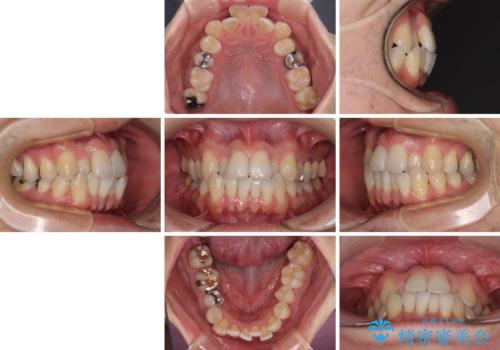

前歯のクロスバイト 目立たないワイヤー装置で矯正治療

- 患者様

- 30代男性

- 矯正装置

- 審美装置

- 治療期間

- 2年2ヶ月

- 前歯のクロスバイトを改善したいとのことで来院された患者様です。

マウスピース矯正では前歯の神経への負担が大きいことを懸念され、ワイヤー装置による矯正治療を行うこととしました。

舌の突出癖が認められたため、デコボコ改善に伴い前歯が前突する可能性があったため、舌のトレーニングをしっかりと行うよう指導しながら治療を進めることとしました。